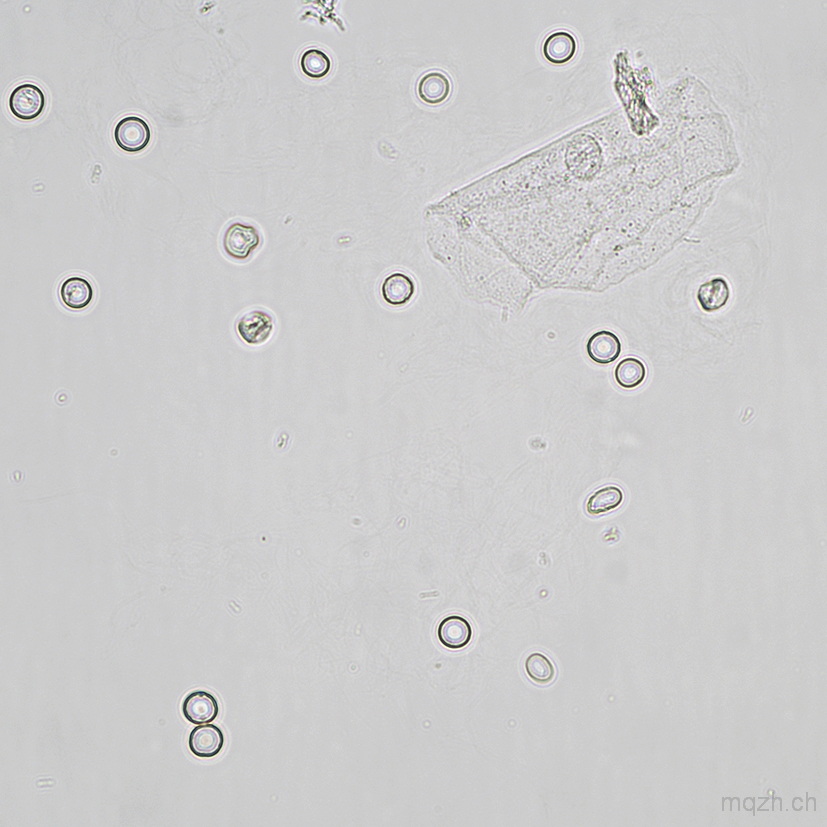

MQ 2026-1 Urinary Sediment U4